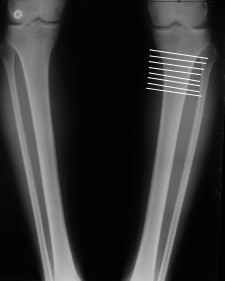

Ещё картинка - схема. Хотя у Соломина всё написано.

Мне представляется оптимальным на уровне 3-4 линии (т.е. как раз посредине отмеченной зоны). Если рассчимтываешь делать медиализацию, то параллельно суставной поверхности, иначе просто не сдвинешь без джистракции - отломки зацепятся. Если без медиализации - то вообще не имеет значения.